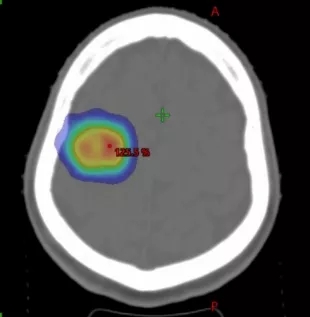

HyperArc治疗颅内多发肿瘤,可一次性照射多个肿瘤靶区,同时确保肿瘤受到充分照射的同时,保护正常脑组织

HyperArc技术使照射肿瘤的角度从原来的360°增加到900°,进一步保护了正常脑组织。在此基础上,肿瘤受到的辐射剂量更大,照射更充分,在保证肿瘤治疗效果的同时再次减轻患者的放疗副反应,使患者在整个放疗过程中更加舒适。

900°照射示意图